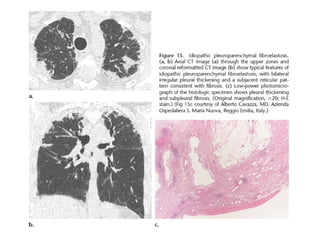

Fibroelastosis

pleuroparenquimatosa idiopática

• Rara

• Fibrosis pelura y subpleura LS

• 60% progresa y 40% muere

• CT:

• Engrosamiento pelural irregular y “tags” y fibrosis

• Pérdiad de volumen de LS, Bq por tracción

• DD: fibrosis pulmonar familiar, tejido conectivo (espondilitis

anquilosante), sarcoidosis fibrótica, neumonitis por

hipersensibilidad

Fibroelastosis pleuroparenquimatosa idiopática • Rara •Fibrosis pelura y subpleura LS • 60% progresa y 40% muere • CT: • Engrosamiento pelural irregular y “tags” y fibrosis • Pérdiad de volumen de LS, Bq por tracción • DD: fibrosis pulmonar familiar, tejido conectivo (espondilitis anquilosante), sarcoidosis fibrótica, neumonitis por hipersensibilidad